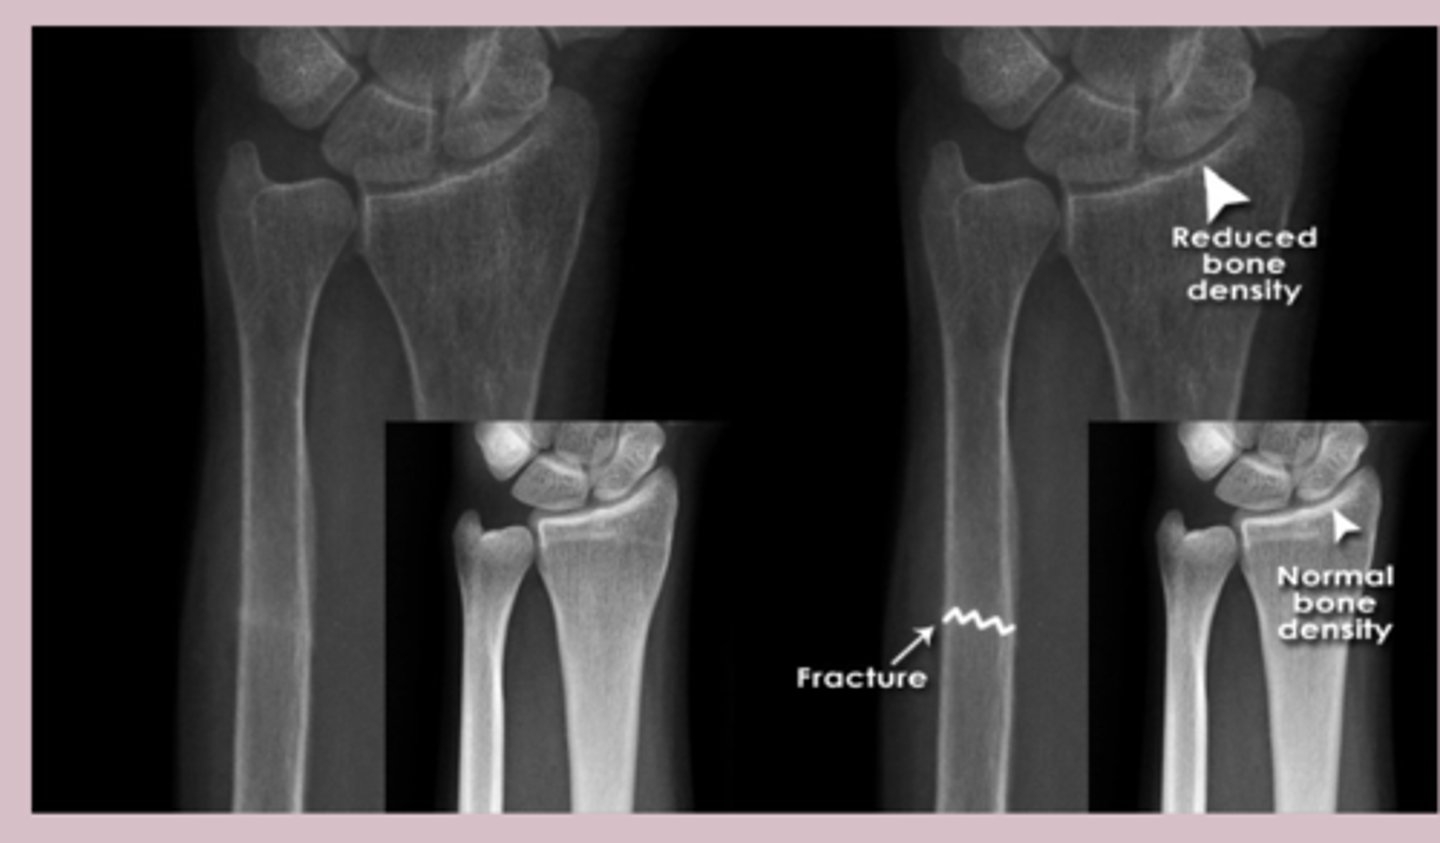

wrist

knowt flashcard image